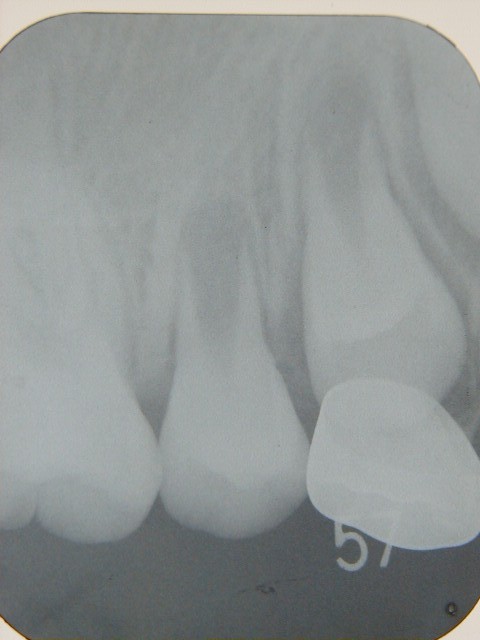

左の写真の白く写っているのが、乳歯に冠をかぶせた歯です。

下から生えてきている永久歯に、押し出されるような状態になっています。

生え変わる寸前のレントゲンです。

乳歯の根っこは、ほとんど永久歯に吸収されてありません。